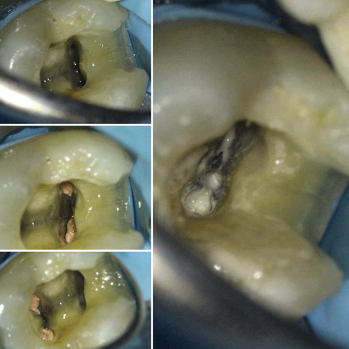

A detailed clinical and radiographic examination (as detailed above) are important to identify the presence of radix entomolaris or radix paramolaris (Figure 6).

The importance of magnification and light cannot be emphasised enough when treating teeth with complex morphology.

The anatomy of the pulp floor is darker in colour. These dark dentine lines provide a helpful ‘map’ to guide the clinician to where the canal orifices are located. A long, sharp endodontic probe (DG16) can then be used to scout the entrance of the canals.

The access cavity will need extending in the direction of the extra canal (RE: disto-lingual or RP: mesio-buccal). A blunt-ended bur (such as an Endo-Z bur) is very useful to enlarge the access as required. Ultrasonics also provide a controlled and conservative way of refining the shape of the access cavity to allow straight line access.

Use fine ultrasonics to conservatively open the isthmus to search for this canal (Figure 7).